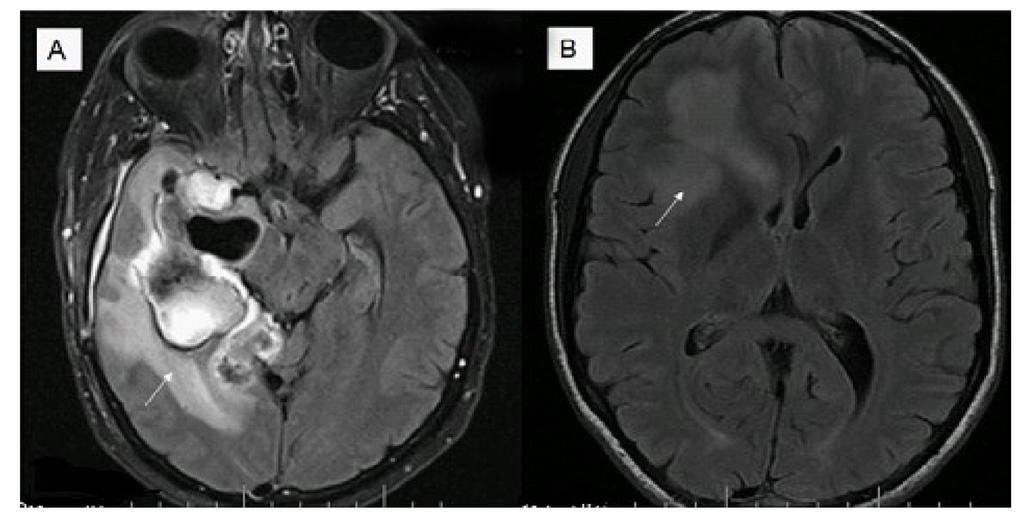

5. Imaging Modalities and Their Potential Biomarker Status